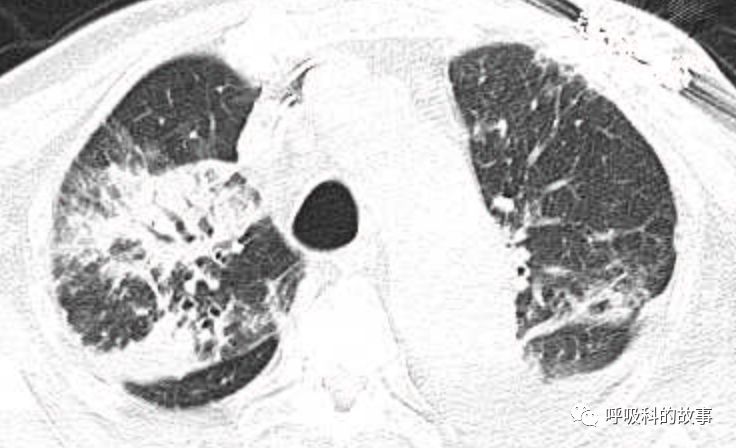

肺部CT如下:

以上的CT给我第一眼的感觉是肺炎,再结合患者有发热和血炎症指标明显增高,肺炎的诊断应该没有问题,但是胸水又是漏出液,结合脑钠肽增高和患者有胸闷气急的症状,心功能不全的诊断也能成立。在某些层面,肺部实变影以内中带为主,还要考虑肺水肿的诊断。入院后给予患者美罗培南抗感染、托拉塞米利尿治疗,以及化痰、雾化处理,患者体温在入院后三天就正常了,入院第五天复查NT-proBNP3390pg/ml;血常规示白细胞 13.5*10^9/L,中性粒细胞81.8%,淋巴细胞13.2%,超敏C-反应蛋白 25mg/L;电解质示钠 160mmol/L,氯 111mmol/L 。虽然炎症指标和心功能指标均有好转,但患者却仍旧精神差,每次查房时仍然表现嗜睡状,家属也反映患者不论白天还是夜晚多数时间不是太清醒。那么问题出在哪里呢?